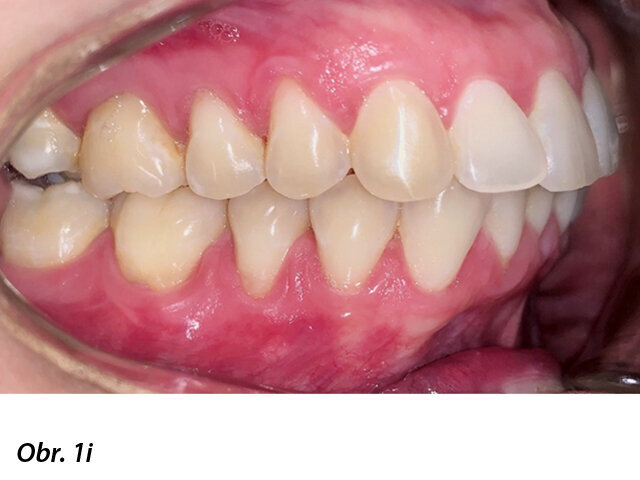

Pacientka 1 – Počáteční fotografie.